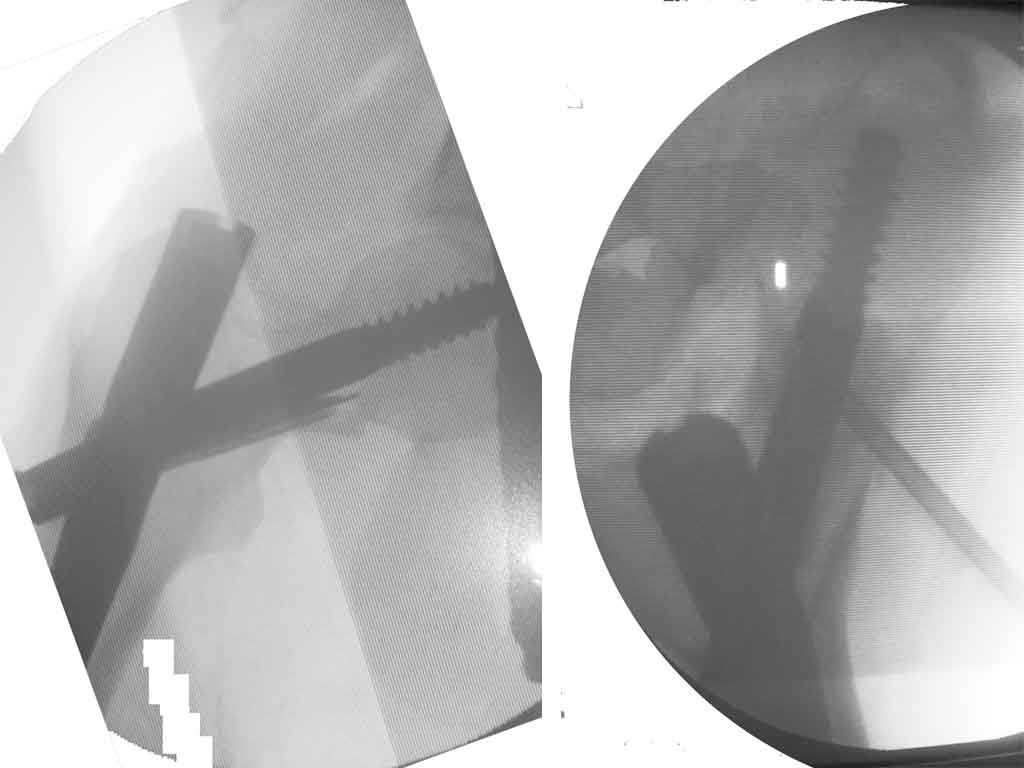

Приносим извинения за молчание. Больная прооперирована: под контролем ЭОП (защита плода несколькими халатами) выполнена закрытая репозиция на ортопедическом столе и фиксация Stryker Gamma 3 nail. Послеоперационные рентгенограммы мы решили не делать, чтобы не давать и без того чрезмерную нагрузку на плод. Поэтому придется довольствоваться картинкой с ЭОПа, правда сделанную на неподходящий для таких условий съемки фотоаппарат.